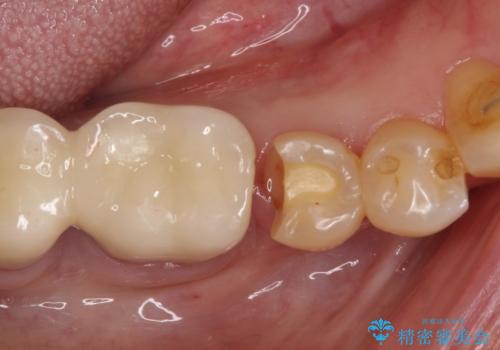

【PGAインレー】深い位置の二次カリエス

- 定期検診にて虫歯を発見したため、PGAインレーにて治療を行いました。